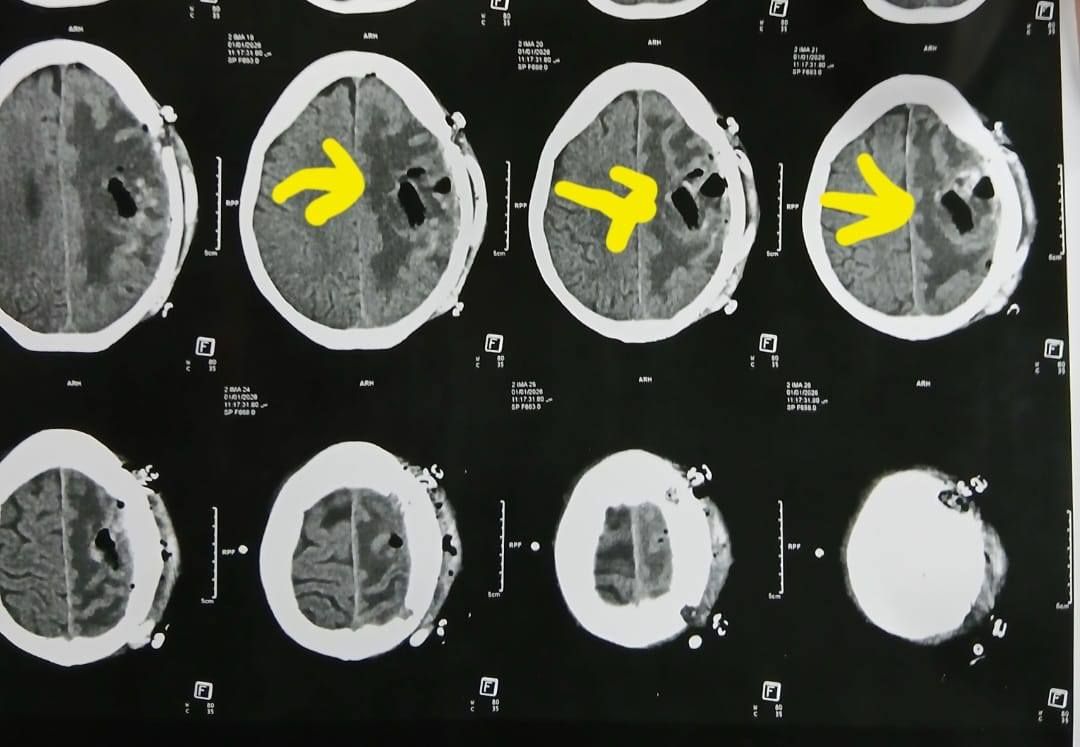

أشعة المريضة

الأشعة الخاصة بالمريضة

الأشعة

وكشف الدكتور إبراهيم الغريب رئيس قسم جراحة المخ والأعصاب بالمستشفى، أنه تعود تفاصيل الحالة إلى استقبال المستشفى المريضة بالعيادة الخارجية وهي تشكو من تنميل وضعف بالجانب الأيمن وثقل بسيط في الكلام، وبإجراء الفحوصات اللازمة من أشعة مقطعية ورنين مغناطيسي بالصبغة، تبين وجود ورم بالمخ، وتم إعطاؤها العلاج المناسب لحين استكمال الفحوصات.